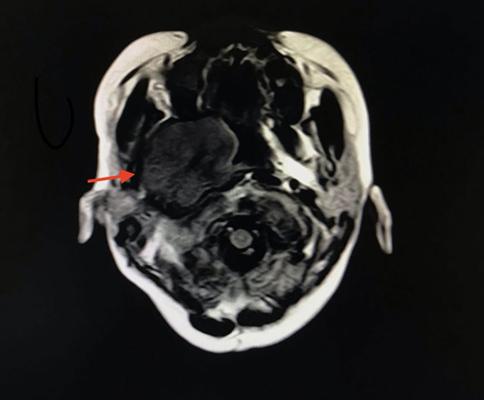

下图便是甜甜的头颅磁共振图像。在孩子的鼻腔后部,生长了一个巨大的肿瘤,大小约4cm×5cm×5cm。

10岁的孩子,整个脑袋的直径也不过15厘米左右,而这个巨大的肿瘤居然占据了那么大的空间,怪不得孩子出现了长时间不能治愈的口角歪斜、不能闭眼、说话瓮声瓮气、咀嚼困难等。甜甜的病因有了眉目,这是一个翼腭窝占位、很可能是一个恶性的肿瘤,我们马上联系了耳鼻喉科,由专业的医生来评估后续治疗。